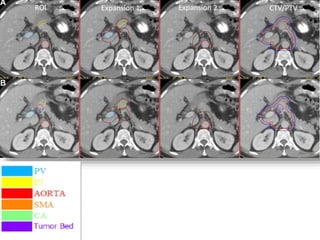

ROI Delineation:Post-op Bed

 Location of tumor should be reviewed and contoured

based on pre-op imaging.

 Surgical clips placed should only be included if there is

documentation from the surgeon intraoperatively such

as close margins or specific tumor related .

ROI Expansions

 Pancreaticojejunostomy, portal vein, superior mesenteric

artery and celiac artery are expanded by 0.5-1 cm.

 Aorta ROI is given asymmetric expansion; 2.5-3 cm

towards right , 1cm towards left, 0.2 cm posteriorly and 2

-2.5 cm anteriorly.

 The CTV is then created by merging the ROI expansions .

 The posterior margin should follow the contour of the

anterior aspect of the vertebral body without including

more than 0.5 cm of the anterior vertebral body anterior

edge.

 If the PJ cannot be identified, the CTV should be

generated

without it.

 If the CTV with the noted expansions protrudes into a

dose limited normal organ such as the liver or stomach or

kidney, it should be edited to be adjacent to the relevant

structure

 PTV – 0.5 cm expansion on CTV